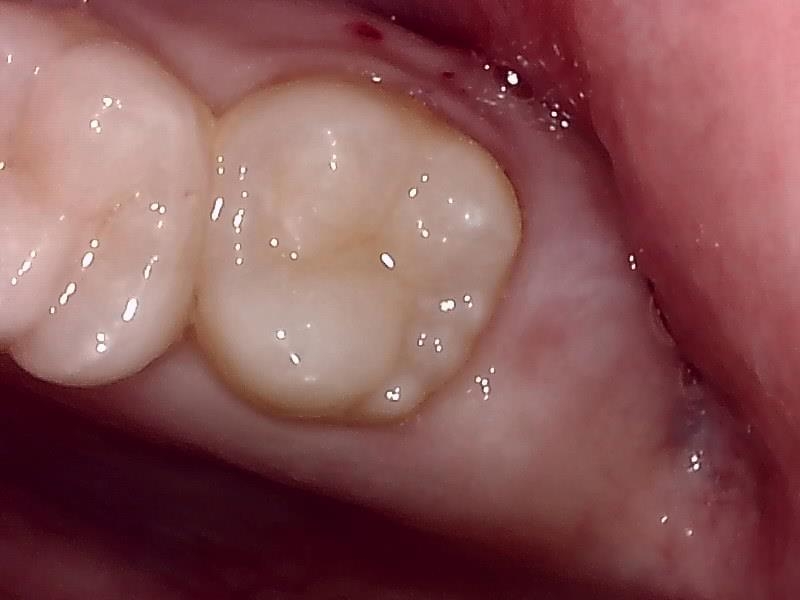

治癒

抜歯後、経過良好です。